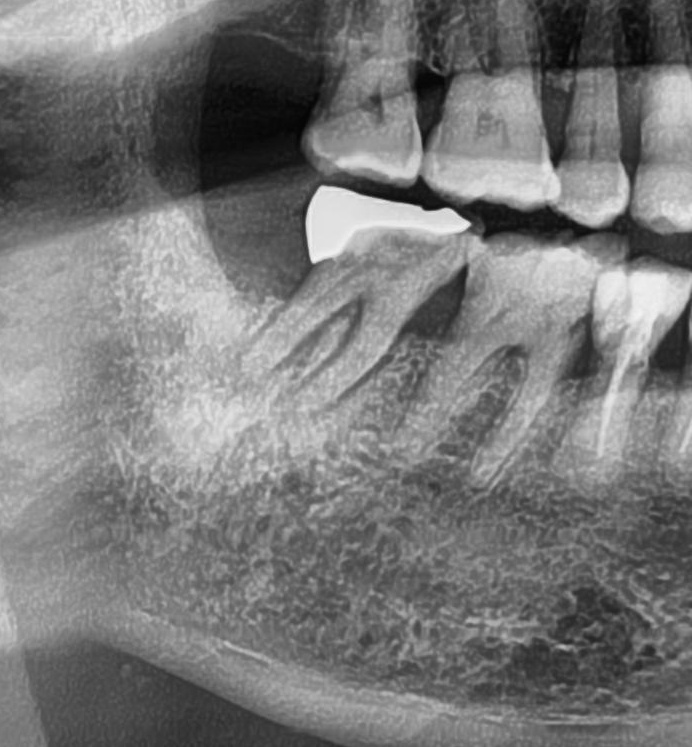

次にパノラマ写真を撮影してみると、親知らずはまっすぐに生えているのが確認できました。

親知らずが生えている位置が、神経に近い、あるいは神経に当たっている場合は、大きな病院に紹介する場合もあります。

親知らずの根っこは下歯槽神経からも十分距離があり、抜歯は可能との診断でした。